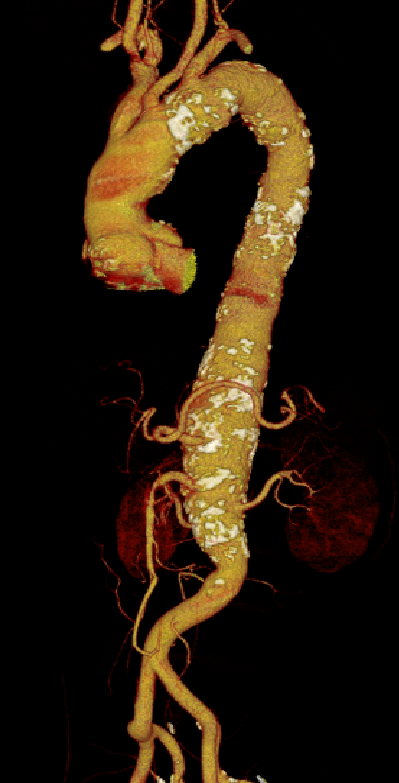

涉及内脏区的主动脉瘤腔内修复是一种顶尖的微创手术技术,主要用于治疗复杂的主动脉瘤。手术的关键在于详细的术前规划、精准的开窗和分支支架置入操作和术后管理,这样才能有效提高手术的成功率,减少并发症的发生。

支架稳定性与预防位移

★ 大动脉瘤

分支支架置入后,需预防分支支架从窗口或内脏动脉脱出。动脉瘤形态变化(如主动脉搏动、内漏致瘤体增大)可能导致支架脱出。

★ 大动脉瘤或偏心性动脉瘤术后

如果突然体位变化,有可能主体支架移位导致分支支架从窗口或内脏血管附着处脱出,引起内脏动脉急性阻塞和缺血。